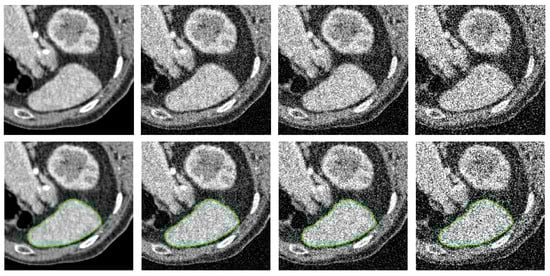

- The PolarMask model does not incorporate contour regularization. In scenarios where image quality is low or distorted by noise, such as in medical CT images, the absence of regularization can lead to unexpected and irregular segmentation results, highlighting significant room for improvement.

- Medical Images: For medical images, we select X-ray computed tomography (CT) scans from [41]. This dataset is commonly used in medical image segmentation evaluations, with image resolution ranging from to pixels, depending on the specific context of each test.

4.2. Qualitative Comparison Analysis

4.5. Performance Under Adverse Conditions